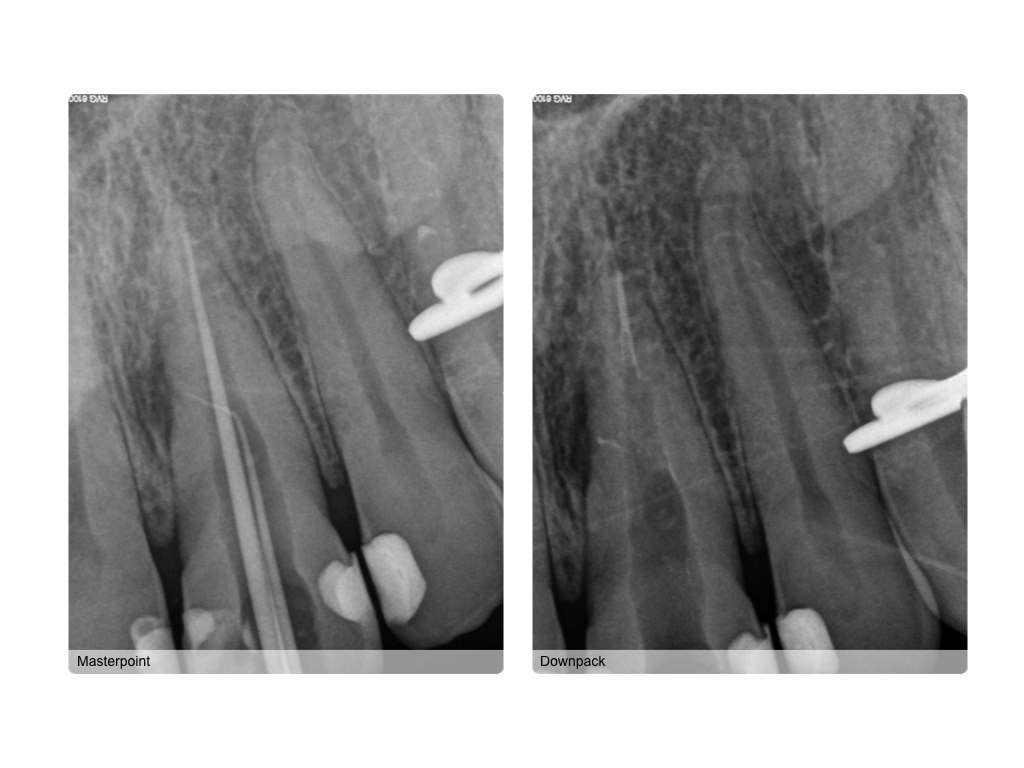

Die Masterpointaufnahme mit der Guttaperchaspitze im lateralen Kanal finde ich toll. Ich bin beeindruckt. Kommentiere ↓